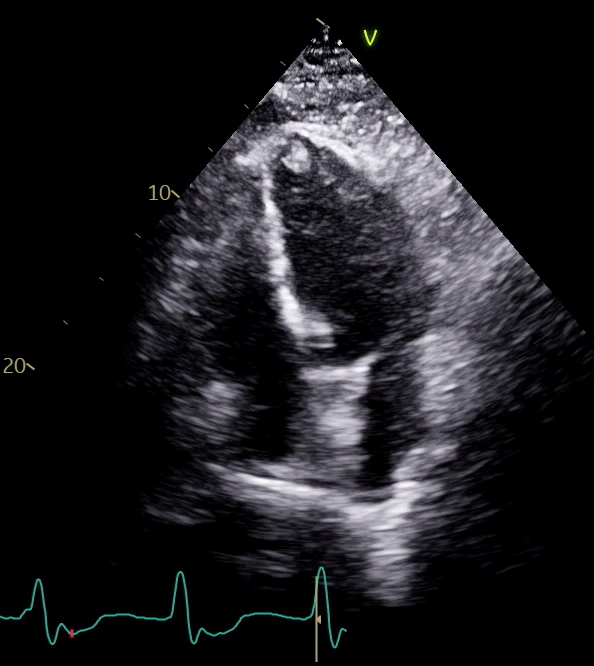

Laboratory study values included high-sensitivity troponin I (hs-TnI) level >25,000 ng/L, creatine kinase (CK) level 11,941 U/L, B-type natriuretic peptide level 224 pg/mL, lactate level 3 mmol/L, C-reactive protein level 1.4 mg/dL, and creatinine level 2.7 mg/dL. An electrocardiogram showed sinus rhythm with complete heart block and ventricular escape (Image 1). An echocardiogram demonstrated left ventricular ejection fraction (LVEF) 25-30%, midapical akinesis, 1.6 x 1.2 cm apical thrombus, and moderate right ventricular dysfunction (Video 1). Right heart catheterization showed equalized pressures (right atrial pressure 12 mm Hg, pulmonary capillary wedge pressure 15 mm Hg) and Fick cardiac index 1.8 L/min/m2. Coronary angiography and endomyocardial biopsy were deferred given clinical instability, acute kidney injury, and high clinical suspicion for the underlying diagnosis.

Video 1: Echocardiogram Showing LVEF 25-30%, Midapical Akinesis, Thrombus Measuring 1.6 x 1.2 cm, and Moderate RV Dysfunction

Video 1

LVEF = left ventricular ejection fraction; RV = right ventricular.